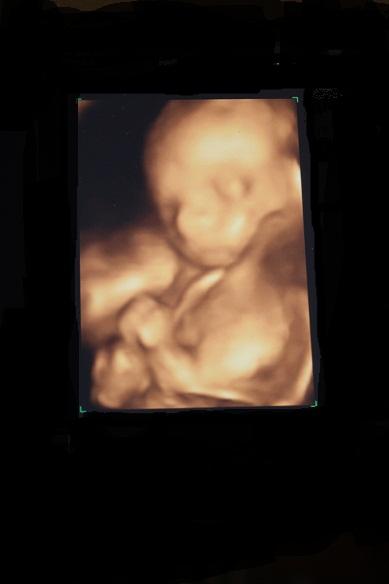

Ich hatte heute einen eigentlich ganz kurzen Termin beim FA. Letzte Woche hatte ich zwei Zecken und der Doc wollte nacch ner Woche die Biss-Stellen nochmal sehen. Alles in Ordnung und in 2Wochen wird das Blut dann kontrolliert, ob wirklich alles in Ordnung ist. Er geht aber davon aus, man kann aber besser auf Nummer sicher gehen. Dann meinte er, ach legen sie sich doch noch hin, dann schauen wir wie es der kleinen Dame geht. allees bestens und sie hat wieder ordentlich rumgeturnt. Leider hat sich die Plazenta noch nicht weiter vom Ausgang entfernt.................Aber Madame ist jetzt etwa 26cm groß und wiegt ca. 440 g! UND es gab nen nettes 3D Bild mit!!!!!!!!!!! Will ich euch mal nicht vorenthalten! LG Wiebke

Bild zu Unverhofft - Forum für Oktober - Mamis